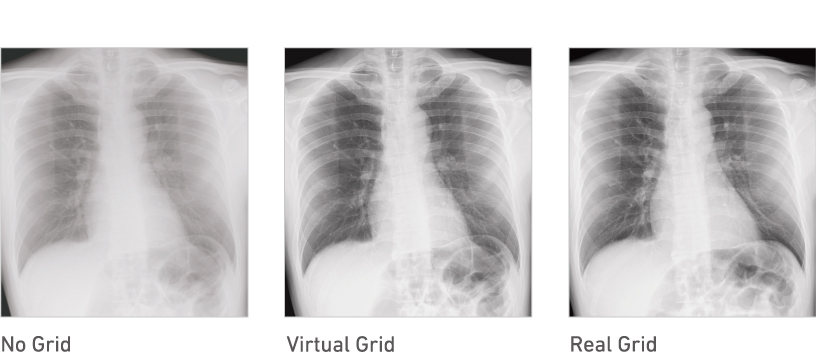

Virtual Grid processing corrects for the effects of scatter radiation. Without the need for a grid, Virtual Grid retains high contrast and image sharpness, while preventing the asymmetric density resulting from misalignment of X-ray tube and detector. (Option)